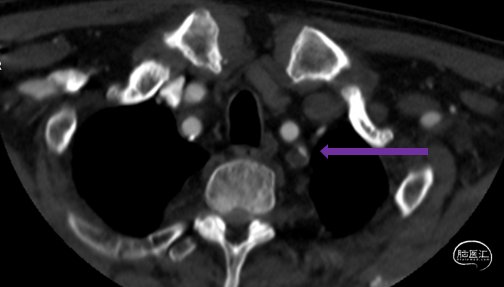

头颈CTA:左侧椎动脉起始、左侧锁骨下动脉重度狭窄。

LSub

LV1

症状性左锁骨下重度狭窄;症状性左椎动脉重度狭窄。